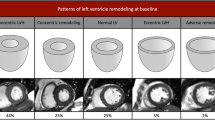

Although echocardiography remains the mainstay imaging technique for the evaluation of patients with valvular heart disease (VHD), innovations in noninvasive imaging in the past few years have provided new insights into the pathophysiology and quantification of VHD, early detection of left ventricular (LV) dysfunction, and advanced prognostic assessment. The severity grading of valve dysfunction has been refined with the use of Doppler echocardiography, cardiac magnetic resonance (CMR), and CT imaging. LV ejection fraction remains an important criterion when deciding whether patients should be referred for surgery. However, echocardiographic strain imaging can now detect impaired LV systolic function before LV ejection fraction reduces, thus provoking the debate on whether patients with severe VHD should be referred for surgery at an earlier stage (before symptom onset). Impaired LV strain correlates with the amount of myocardial fibrosis detected with CMR techniques. Furthermore, accumulating data show that the extent of fibrosis associated with severe VHD has important prognostic implications. The present Review focuses on using these novel imaging modalities to assess pathophysiology, early LV dysfunction, and prognosis of major VHDs, including aortic stenosis, mitral regurgitation, and aortic regurgitation.

Mehrotra, P. et al. Differential left ventricular remodelling and longitudinal function distinguishes low flow from normal-flow preserved ejection fraction low-gradient severe aortic stenosis. Eur. Heart J. 34, 1906–1914 (2013).